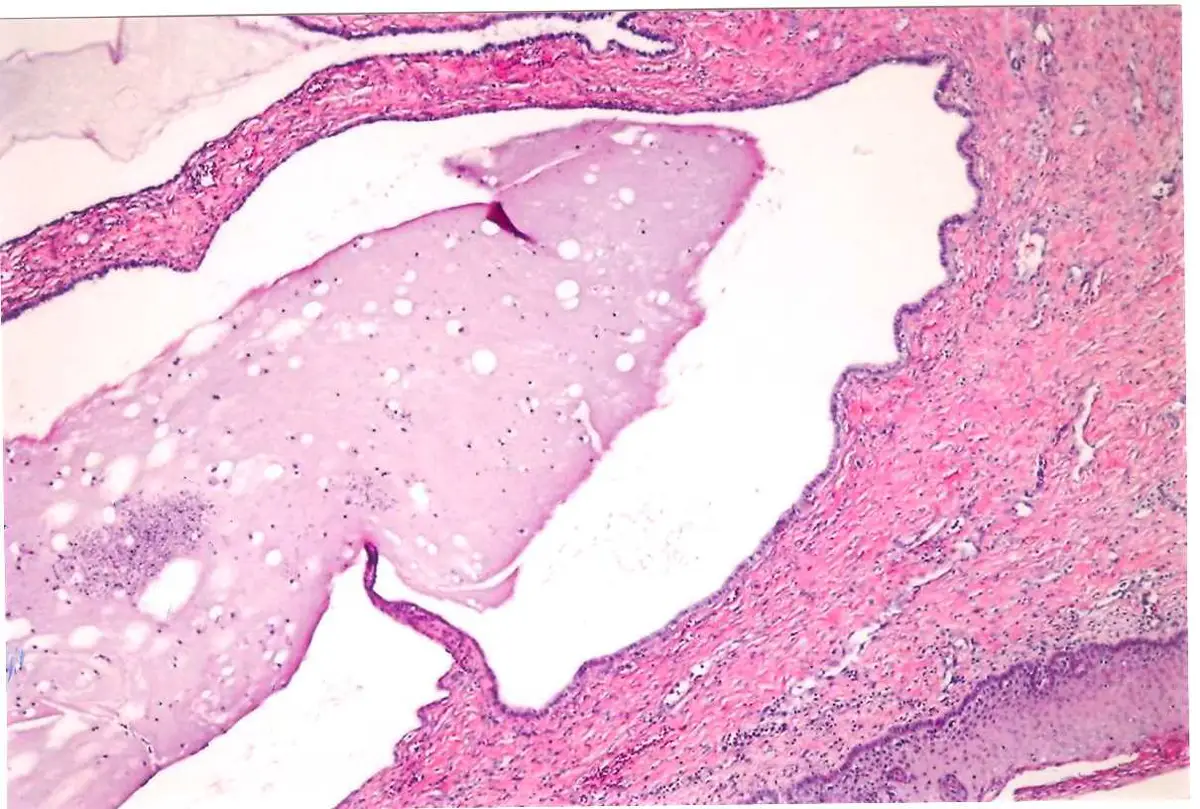

圖片為 H&E(蘇木精-伊紅)染色的組織切片,低倍鏡觀察:

- 囊腔結構:可見一個大型囊狀腔隙,腔內充滿淡染的均質黏液性分泌物(mucinous content),即清澈至淡粉色的膠狀物質

- 上皮襯裡:囊腔壁由單層扁平至立方/柱狀上皮覆蓋,細胞排列整齊,無細胞異型性(atypia)、無核分裂象(mitotic figure),細胞核小且基底化(basally located),符合黏液性柱狀上皮的特徵

- 間質:囊腔周圍為纖維性基質(fibrous stroma),可見少量慢性發炎細胞浸潤(lymphocytes),無明顯急性發炎或壞死

- 整體判讀:無細胞多形性、無腫瘤性增生、無病毒包涵體(inclusion body)、無滴蟲蟲體,完全符合良性黏液性瀦留囊腫(benign mucinous retention cyst)的形態,即納波德氏囊腫的典型病理影像。